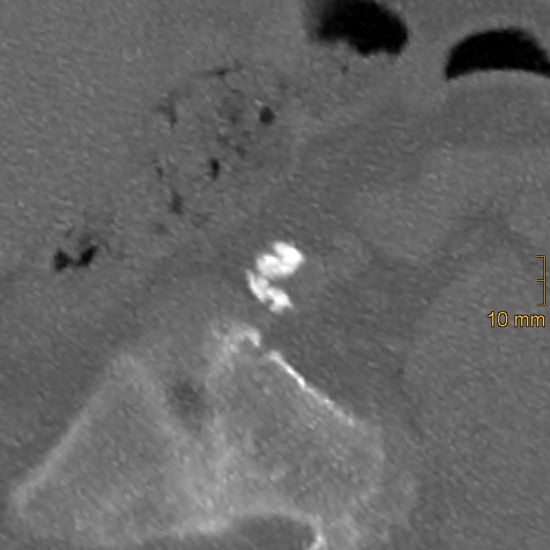

2.2. Assessment of Vascular Calcification

2.2.2. Iliac Artery Calcification